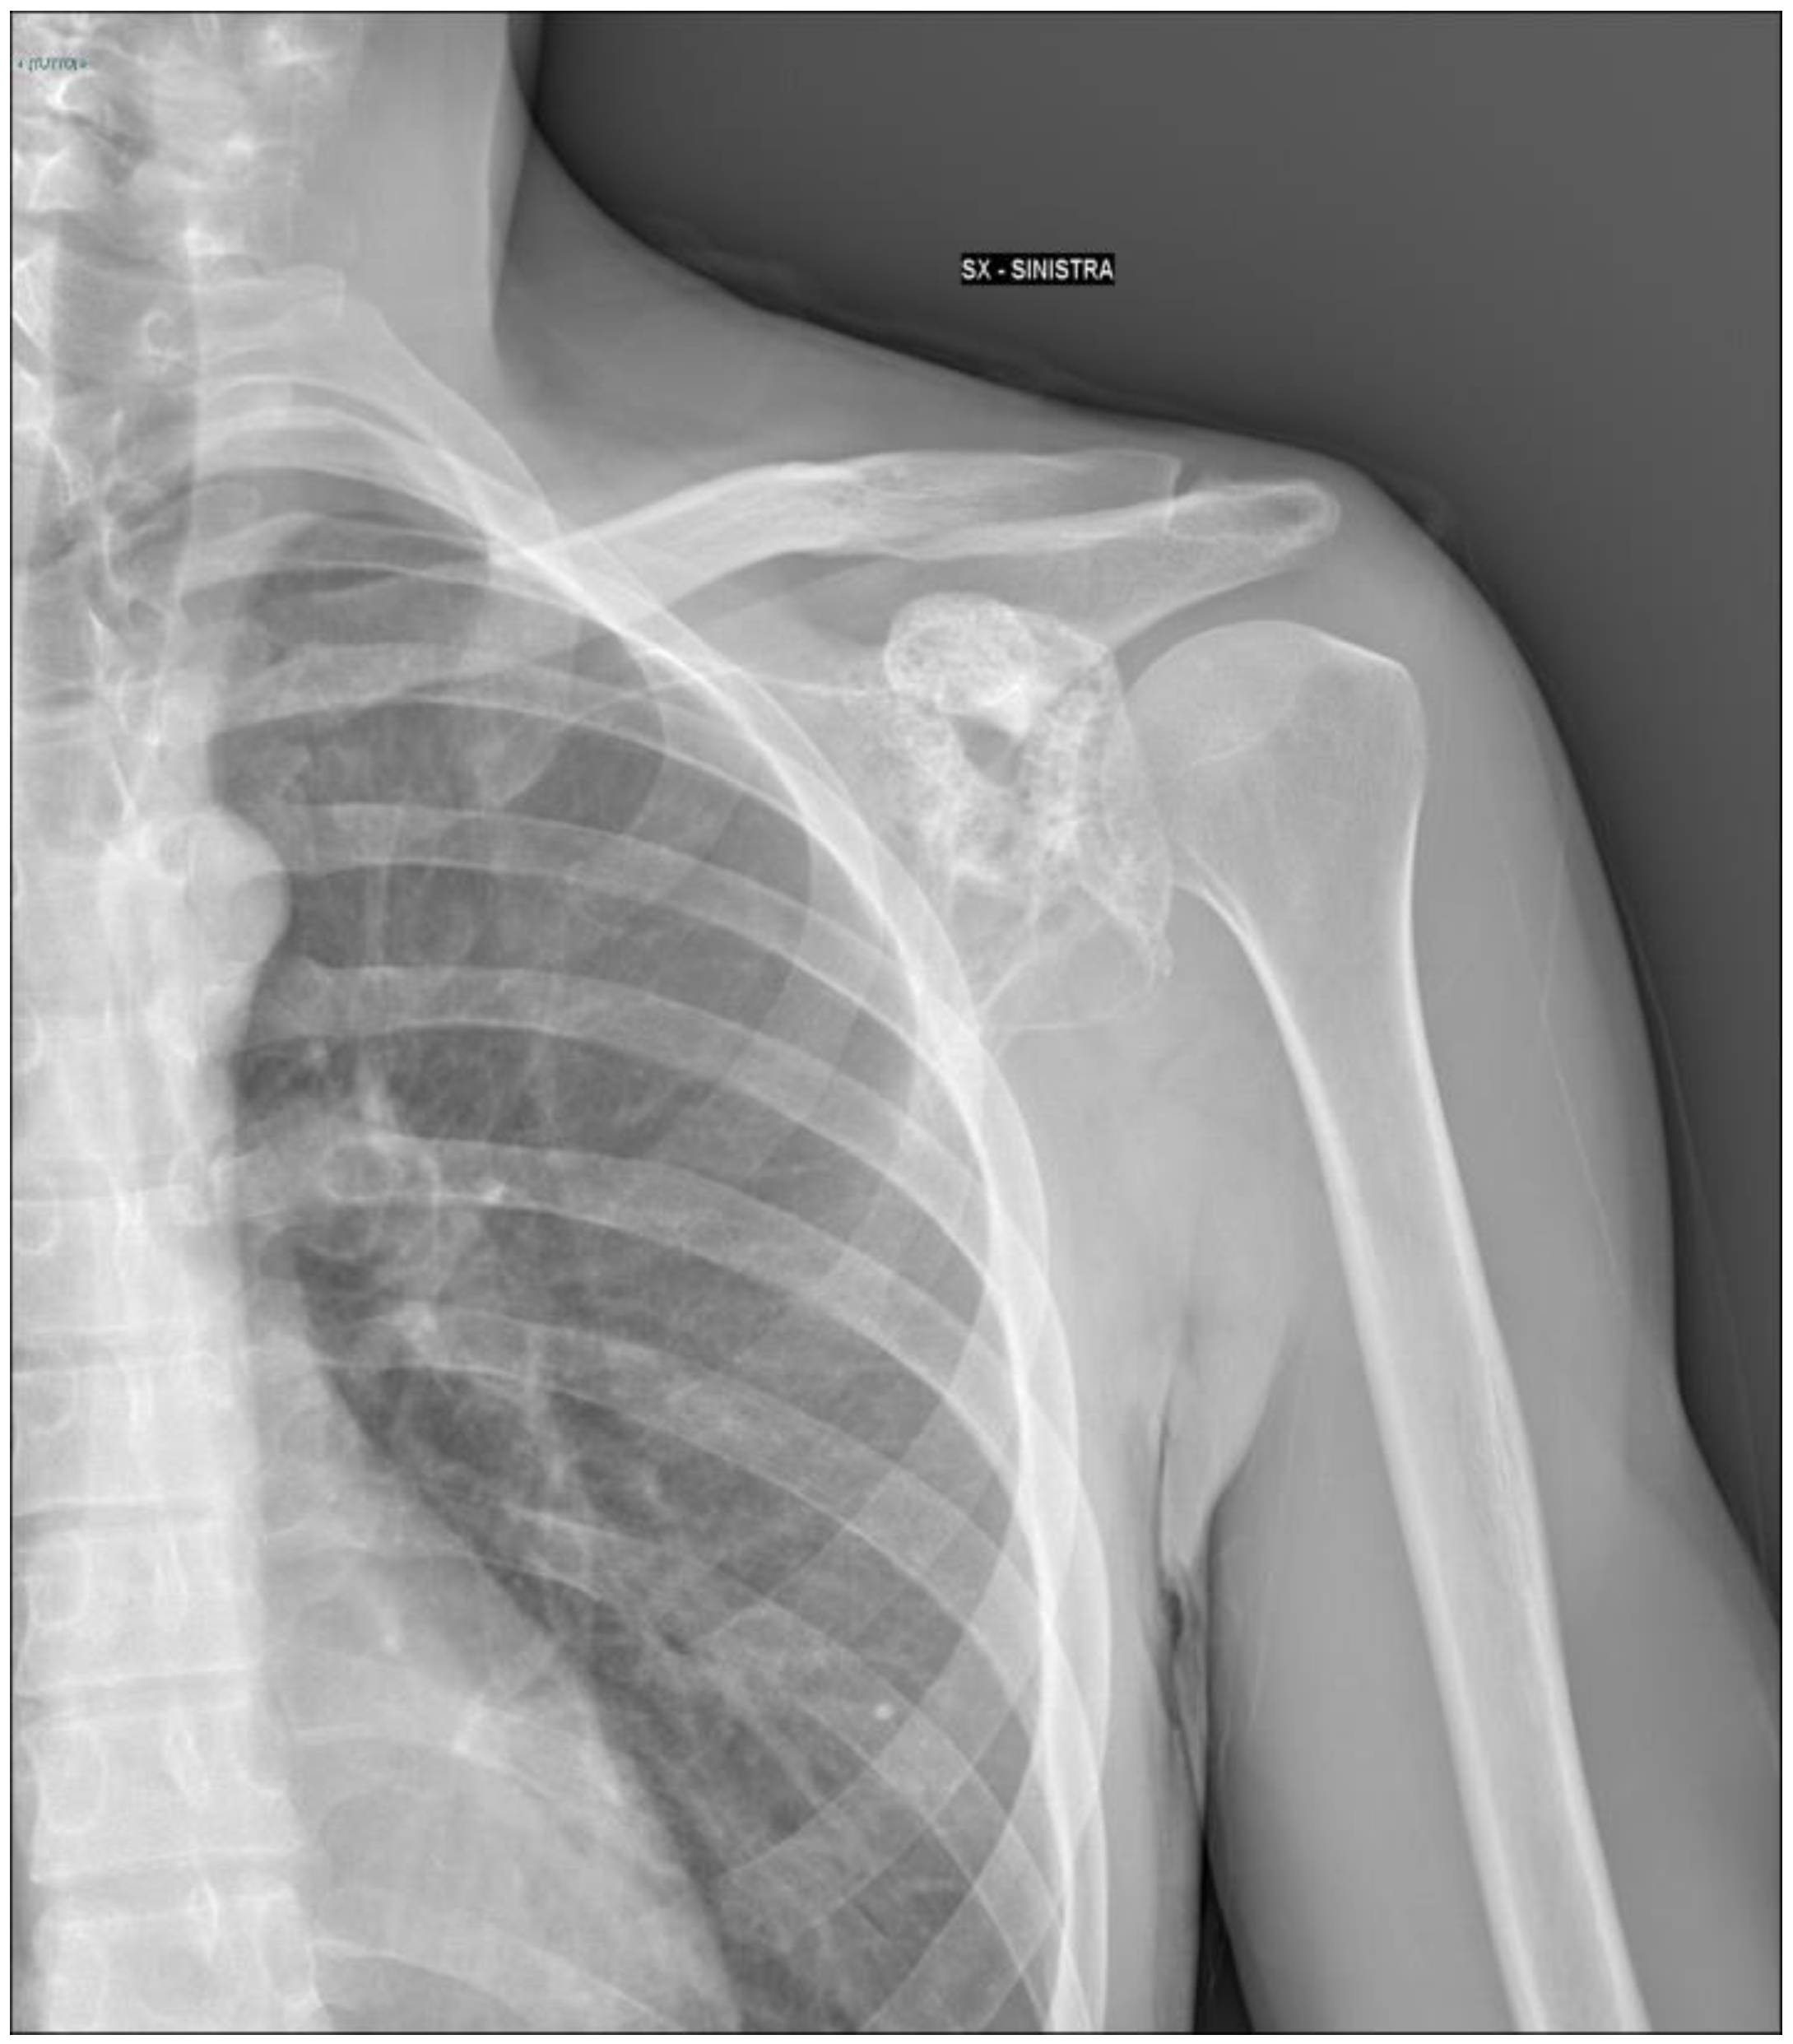

2. Detailed Case Description

2.1. Oncological Staging